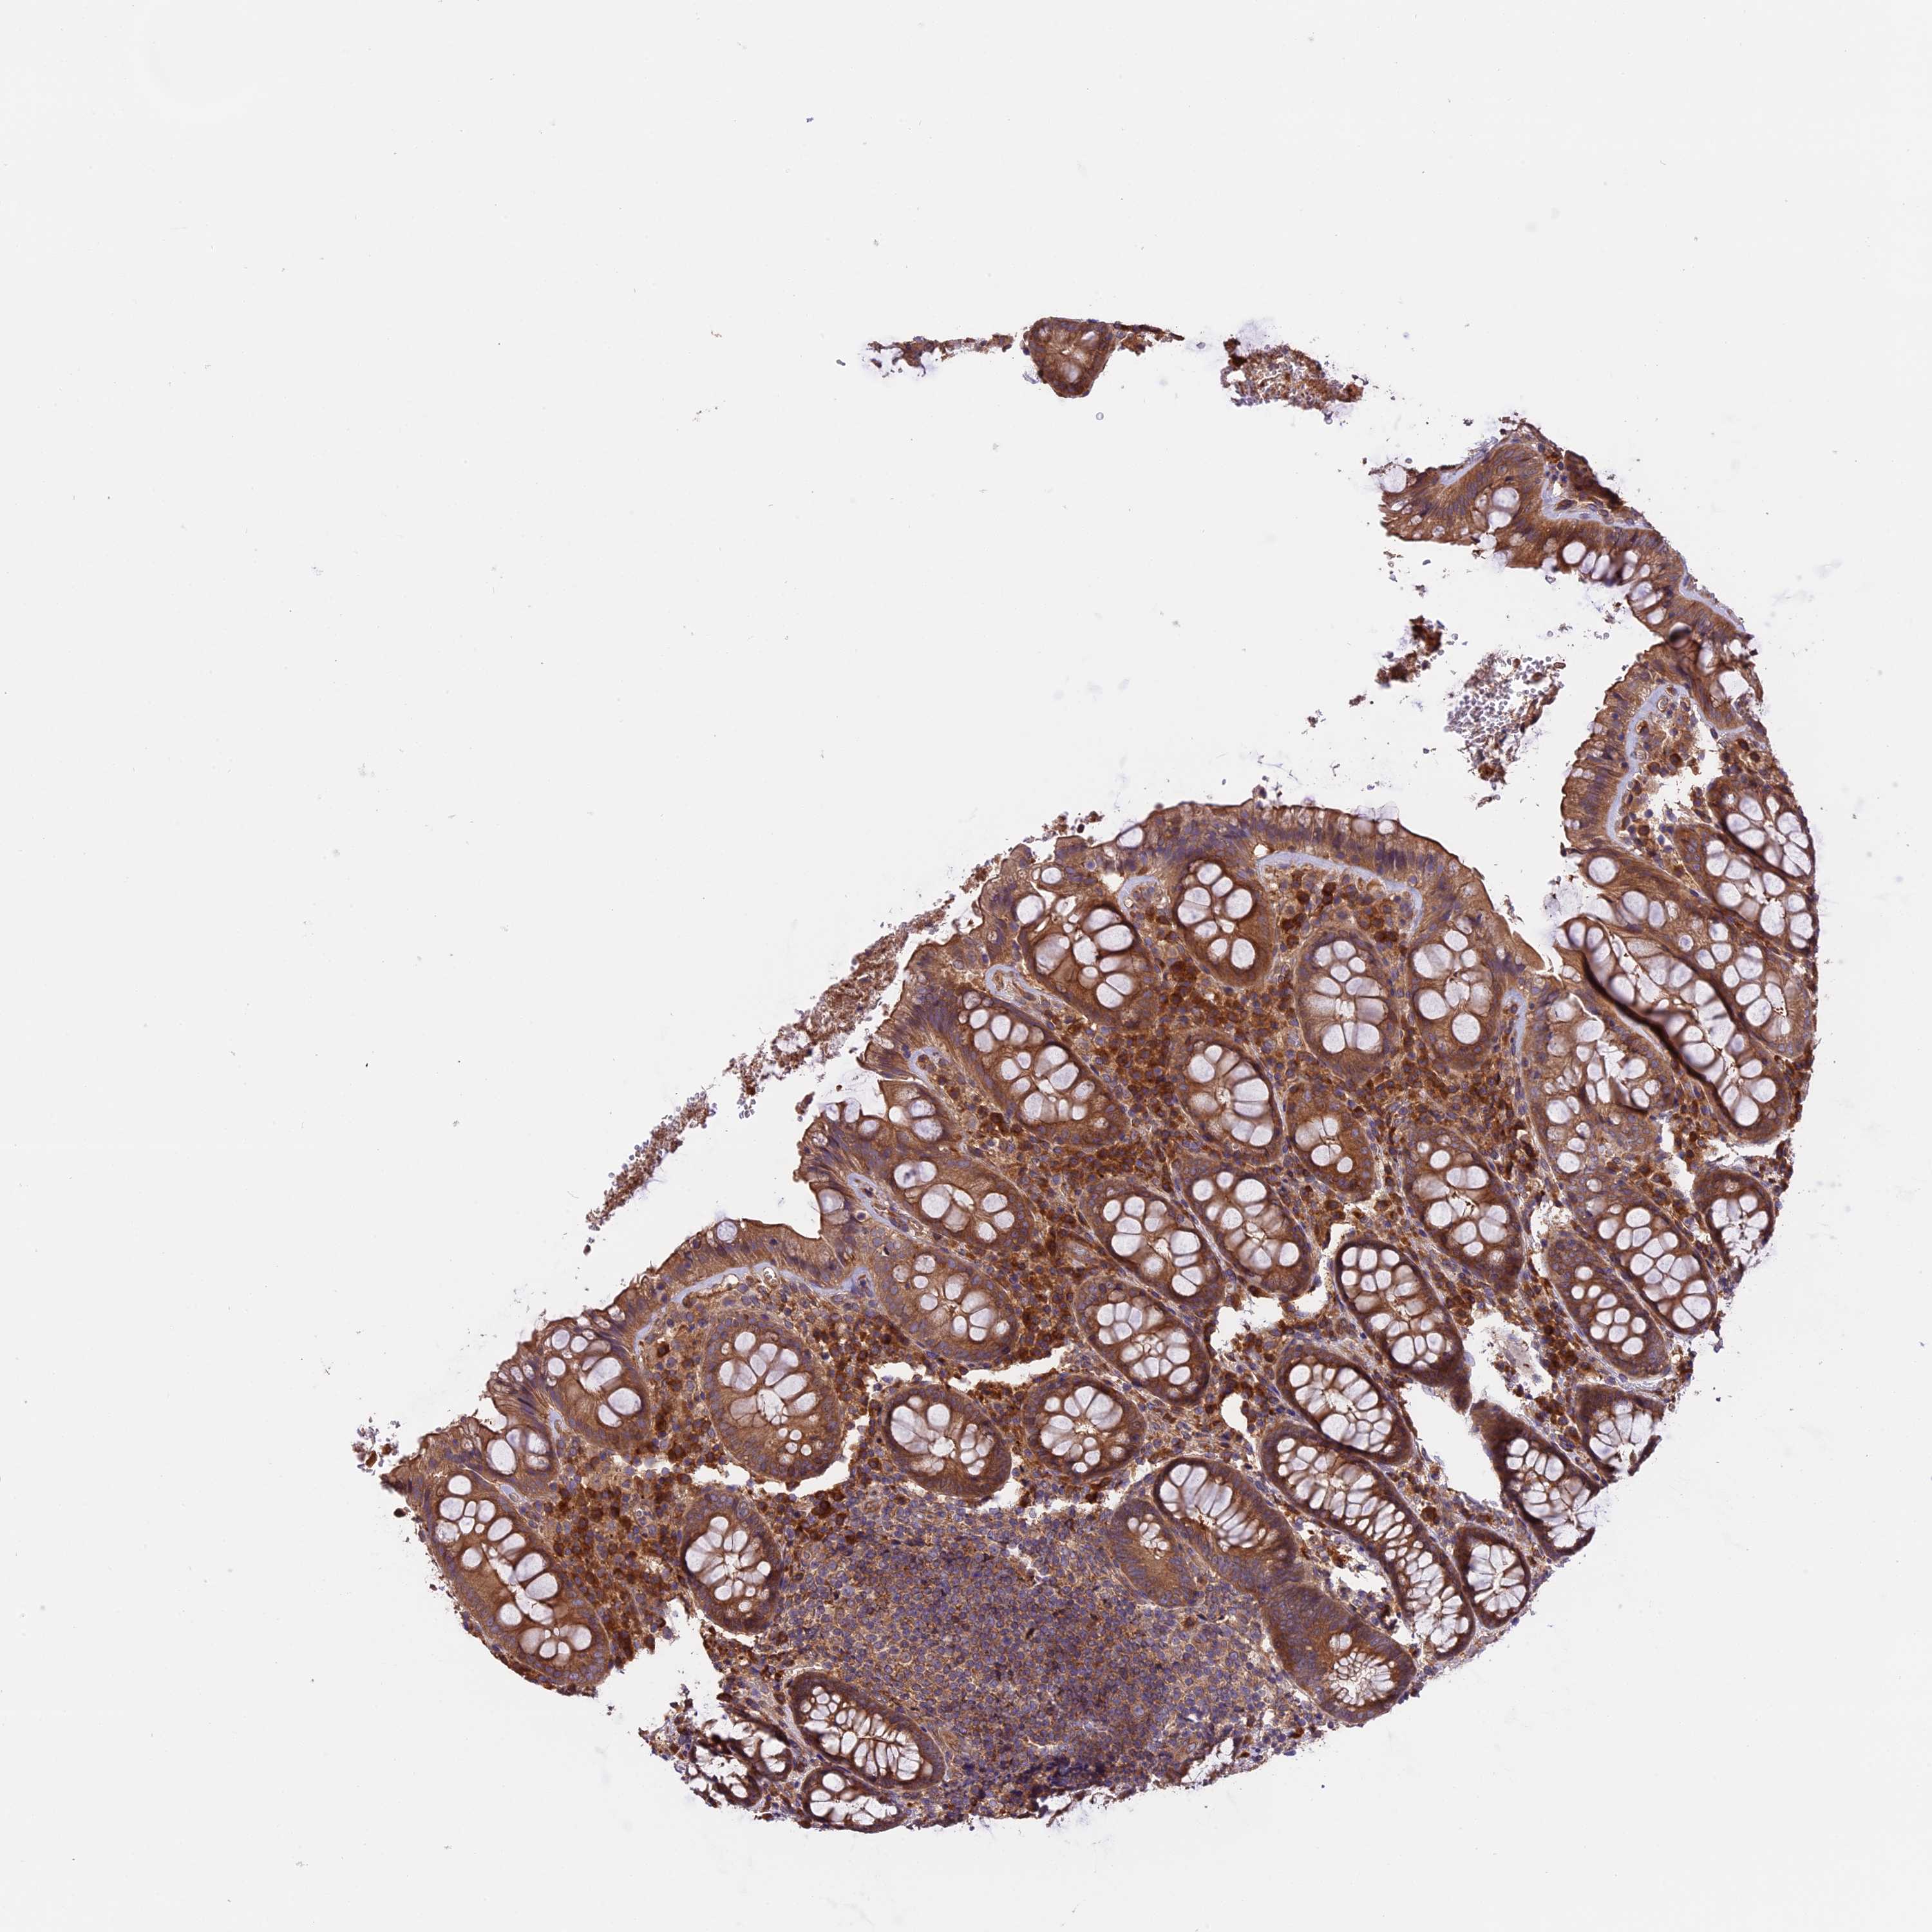

SETD6